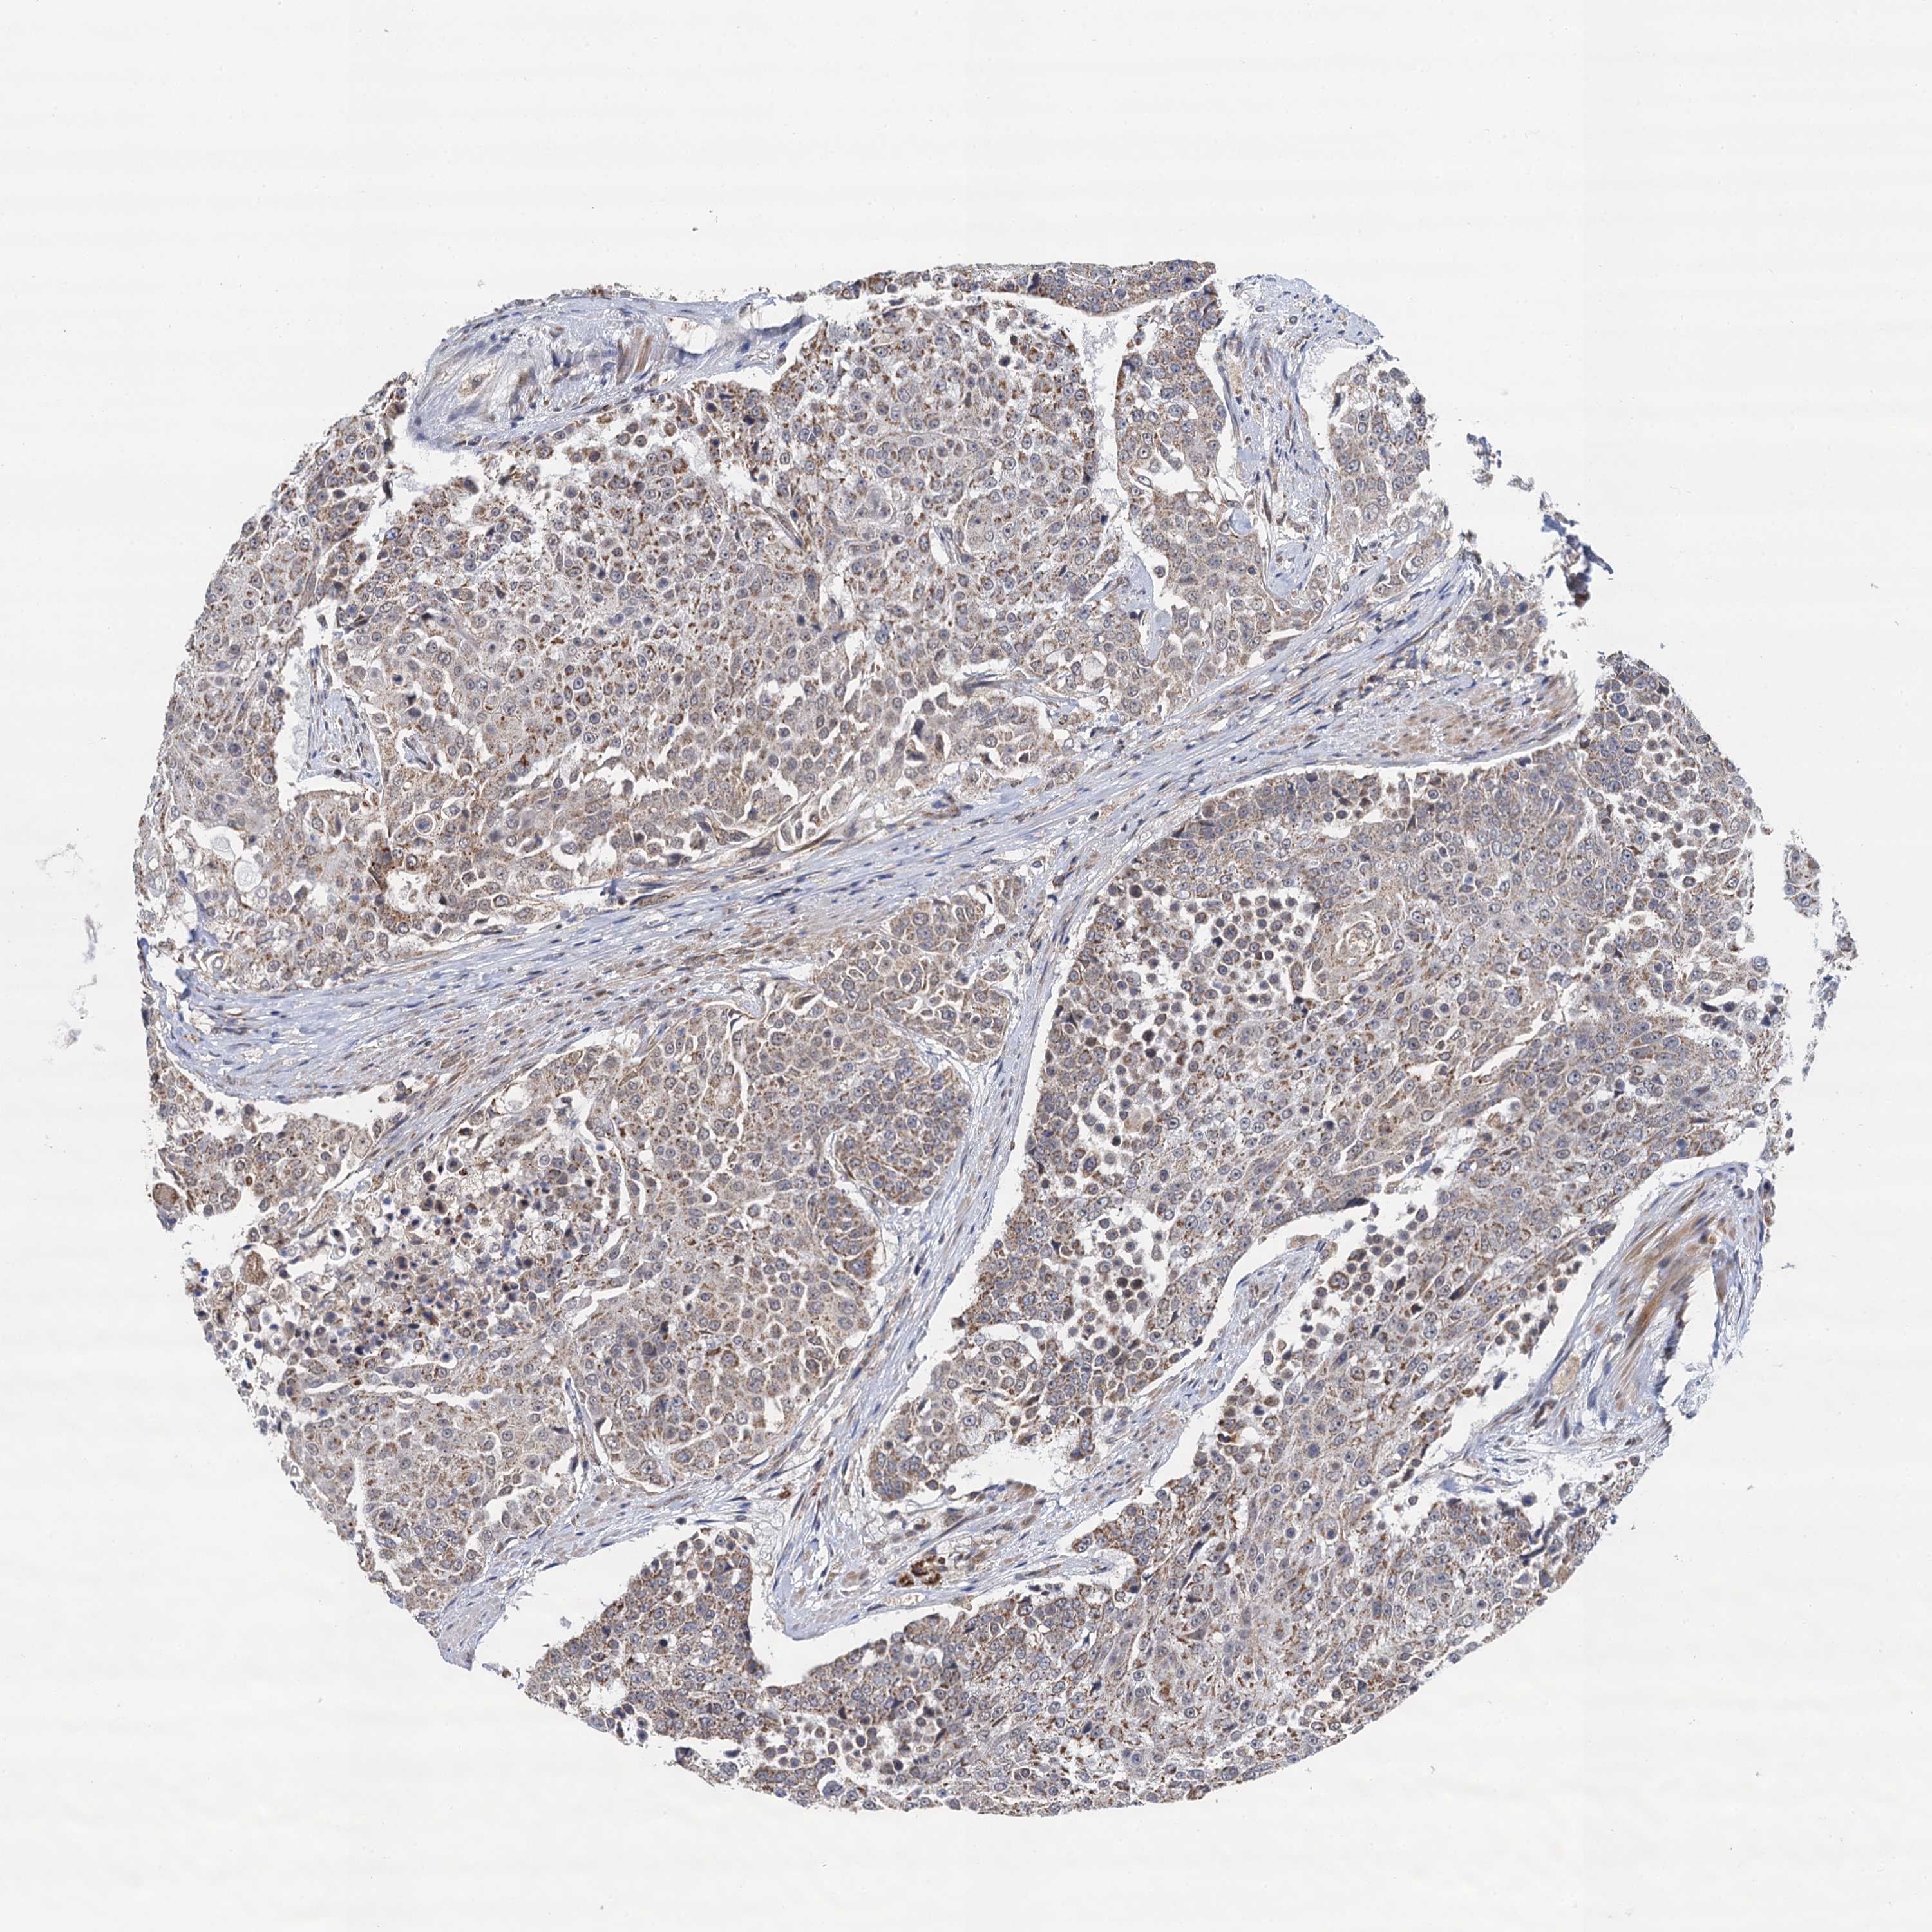

UROTHELIAL CANCER - Protein expressioni

A mouse-over function shows sample information and annotation data. Click on an image to view it in a full screen mode. Samples can be filtered based on level of antibody staining by selecting one or several of the following categories: high, medium, low and not detected. The assay and annotation is described here.

Antibody stainingi

Antibody staining in the annotated cell types in the current human tissue is reported as not detected, low, medium, or high, based on conventional immunohistochemistry profiling in selected tissues. This score is based on the combination of the staining intensity and fraction of stained cells.

Each image is clickable and will lead to virtual microscopy that enables deeper exploration of all samples and also displays staining intensity scores, fraction scores and subcellular localization as well as patient and tissue information for each sample.

Antibody HPA041430

Antibody HPA062191

Staining

High

Medium

Low

Not detected

Intensity

Strong

Moderate

Weak

Negative

Quantity

>75%

75%-25%

<25%

None

Location

Nuclear

Cytoplasmic/membranous

Cytoplasmic/membranous,nuclear

Urothelial carcinoma, High grade

Urothelial carcinoma, Low grade